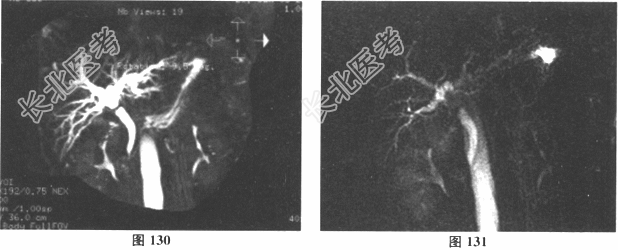

- [材料题] 女性,55岁。主诉腹腔镜胆囊切除术后3个月,皮肤巩膜黄染伴瘙痒20余天入院。3个月前在当地医院行LC术,术后因"胆漏"再次手术,发现"胆管小破口",予"缝合胆管破口+T形管引流术",术后1.5个月复查肝功正常后拔出T形管。拔管后2周出现皮肤巩膜黄染。无发热、寒战,有恶心、呕吐,间断有上腹部疼痛,无腹泻,无大便颜色变浅。当地医院MRI检查提示"肝内外胆管扩张"。病来无明显体重减轻。有高血压病史6年,平素口服苯磺酸氨氯地平片控制血压,血压时有波动。入院后化验:Hb129g/L,WBC5.44×109/L,N0.67,PLT362×109/L,PT11.3s,ATPP39.1s,PTA149%,INR0.82,Fib4.58;ALT419.6U/ml,AST330.5U/ml,Alb38.5g/L,TB141.9μmol/L,DB111.5μmol/L,TBA261.2μmol/L,AKP780.3U/L,GGT1627U/L;AFP4.36ng/ml,CEA0.37μg/ml,CA19-918.5U/ml;乙肝(-)。CT和MRCP检查结果见图。

- 多项选择题1.请问该患者的临床诊断为( )

- 多项选择题2.该患者胆管损伤的Bismuth分型为( )